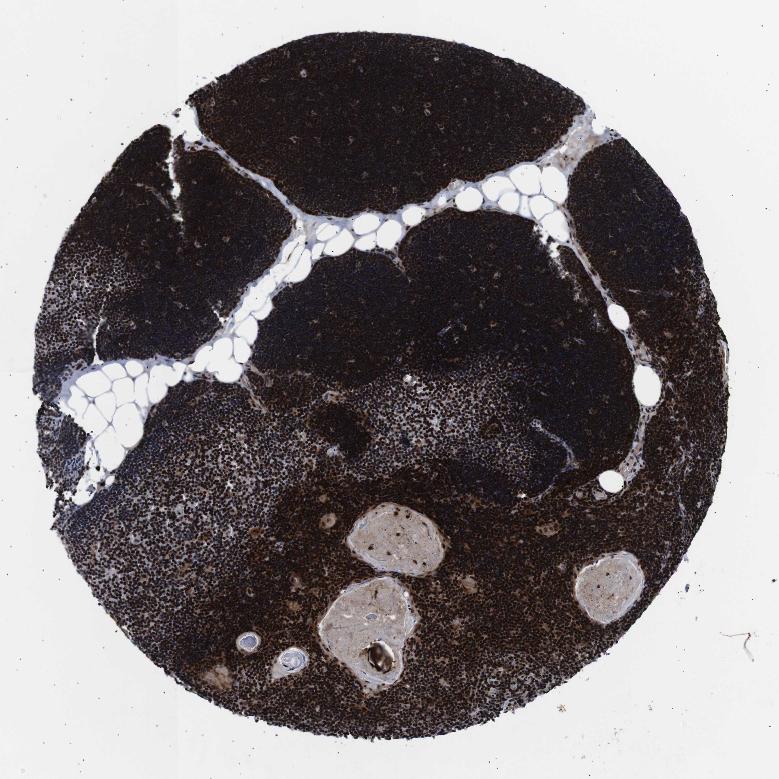

TISSUE PRIMARY DATA LYMPH NODE Show tissue menu

Lymph node

LYMPH NODE - Antibody stainingi

Antibody staining in the annotated cell types in the current human tissue is reported as not detected, low, medium, or high, based on conventional immunohistochemistry profiling in selected tissues. This score is based on the combination of the staining intensity and fraction of stained cells.

Each image is clickable and will lead to virtual microscopy that enables deeper exploration of all samples and also displays staining intensity scores, fraction scores and subcellular localization as well as patient and tissue information for each sample.

Antibody CAB010414

Germinal center cells Medium

Non-germinal center cells High